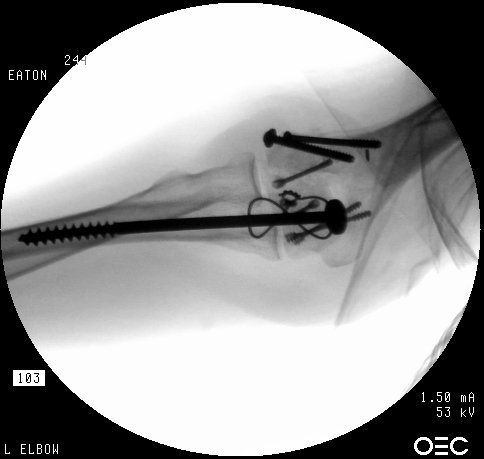

The olecranon osteotomy was closed with a 6.5 mm lag screw and (belt and suspenders) tension band technique.

Click for larger image

Anatomic reduction.